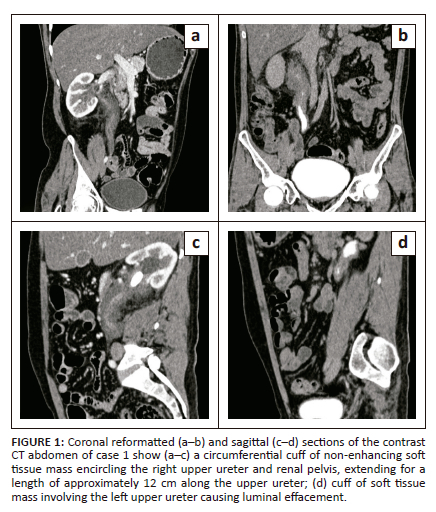

A 35-year-old male who was recently diagnosed with bilateral nephrolithiasis was referred for CT urography. The images obtained revealed multiple, hyperdense calculi in the right renal pelvis, the largest measuring 28 mm × 21 mm with a mean attenuation value of 1230HU. There was associated marked peripelvic fat stranding and a cuff of non-enhancing soft tissue encircling the right upper ureter and renal pelvis, measuring 33 mm × 28 mm (Anteroposterior [AP] × transverse) extending for a length of approximately 12 cm along the upper ureter (Figure 1a-c). The left kidney revealed a 7 mm × 8 mm hyperdense calculus with a mean attenuation value of 780HU in the left upper ureter with a similar non-enhancing soft tissue mass cuffing the left renal pelvis and upper ureter for a length of 7 cm - 8 cm, maximum AP and transverse diameters of 23 mm × 12 mm, respectively (Figure 1d).

CT-guided fine needle aspiration and biopsy revealed a few focal areas of stromal fibrosis without any evidence of malignancy. Initial blood serology was unremarkable. An autoimmune profile was requested, including serum IgG4 levels, which revealed markedly elevated serum IgG4 levels (> 300 mg/dL). The patient underwent bilateral double-J (DJ) stent insertions and was commenced on corticosteroid therapy for IgG4-RD.